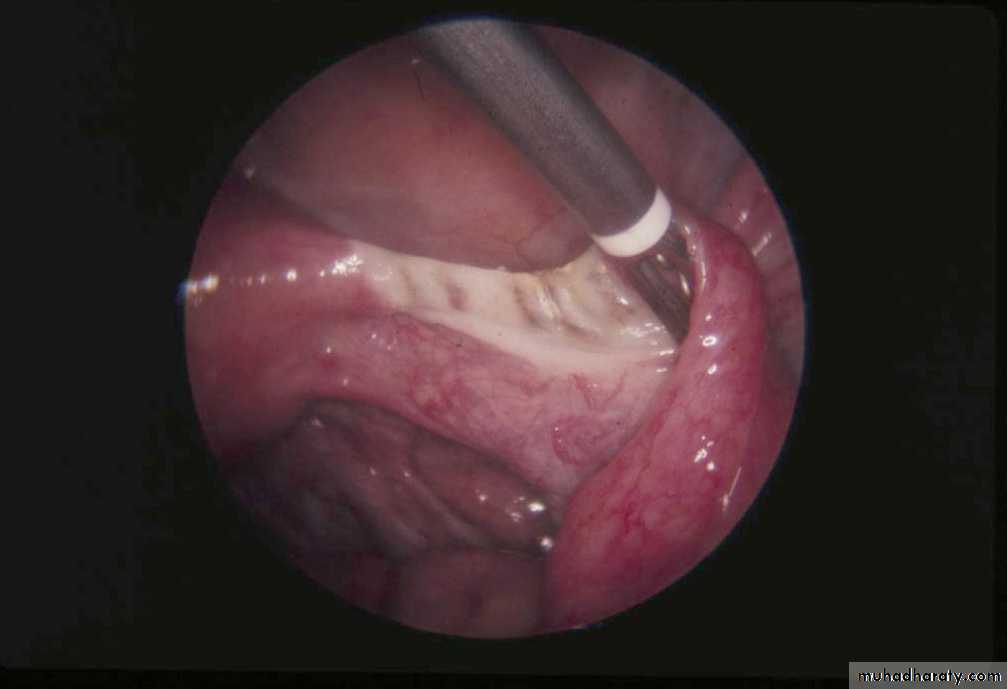

Monopolar coagulation

• It is laparascopic procedure

• Complications• Bowel Burn

• Bleeding

• Longer portion of tube is damaged

• Failures and ectopic pregnancy

Bipolar coagulation

• Laparoscopic• Benefits

• Most common method of laparoscopic sterilization

• Burn several locations along the tube

• Complications

• High rate of ectopic pregnancy

• Potential for bowel burns

• Reversals are potentially more difficult due to the extent of tube damage

Destruction of the Entire Fallopian Tube: “Three Burn” Technique